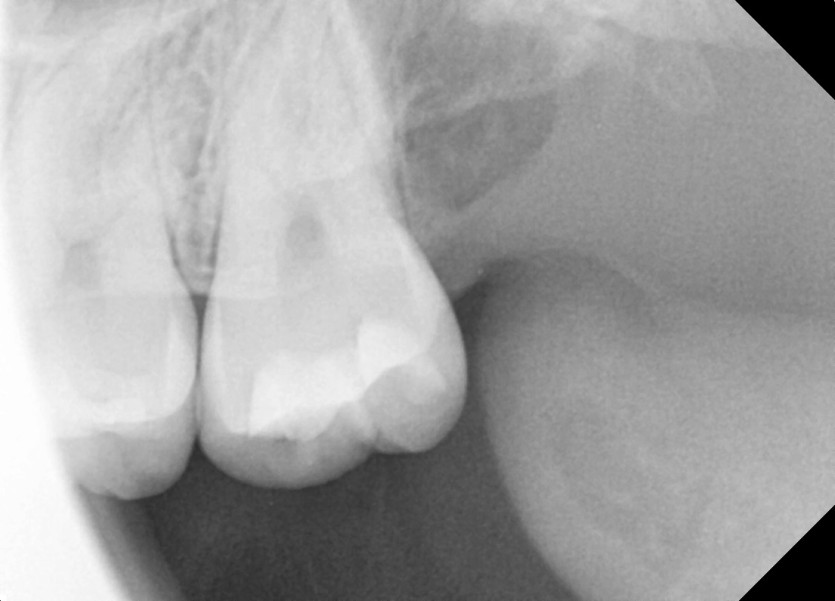

#28,38 사랑니 발치

구강 외과 전문의가 당일 발치했습니다.